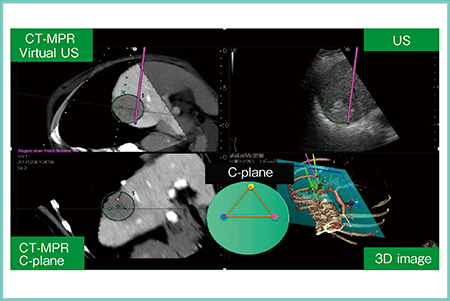

症例3は,84歳,女性。肝S7に4.5cmの肝細胞がんが認められ,TACE併用にて,ダブルトライアングル法を用いてRFAを施行した。本法は,まず腫瘍に3本の電極針を二等辺三角形に配置してシミュレーションを行い(図4),その後,三角形の頂点に当たる電極針(黄色)を逆三角形の頂点となる位置に再配置してシミュレーションを行ってから焼灼する(図5)。治療後のCTにて十分なマージンが確認でき,再発も認められていない。

図4 症例3:肝細胞がん症例へのダブルトライアングル法でのバイポーラRFA